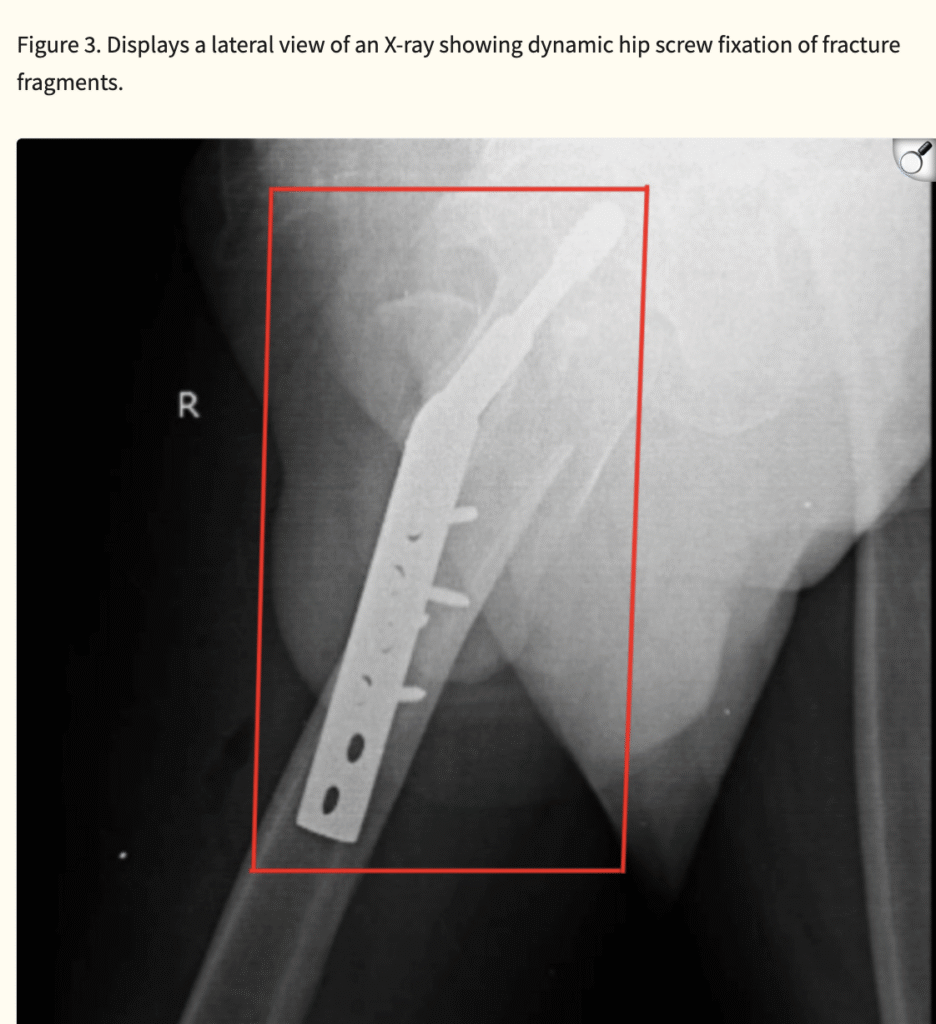

Intertrochanteric fractures are increasingly prevalent as life expectancy rises worldwide. Osteoporosis and accidental falls remain the leading risk factors among older adults. While surgical stabilization is the treatment of choice, complications such as infection, non-union, avascular necrosis, venous thrombosis, and post-traumatic arthritis may hinder recovery.

Even with surgical intervention, nearly half of patients fail to regain pre-injury mobility. Thus, rehabilitation plays a pivotal role in restoring function, maintaining independence, and preventing long-term disability. Early stabilization of hip fractures allows for quicker mobilization, shorter hospital stays, and reduced complications, ultimately improving survival and quality of life.

Physiotherapy contributes substantially to recovery by addressing pain, swelling, joint stiffness, muscle weakness, impaired coordination, and balance deficits. Progressive strengthening, gait training, and functional retraining help patients regain mobility and confidence, reducing the risk of recurrent falls.